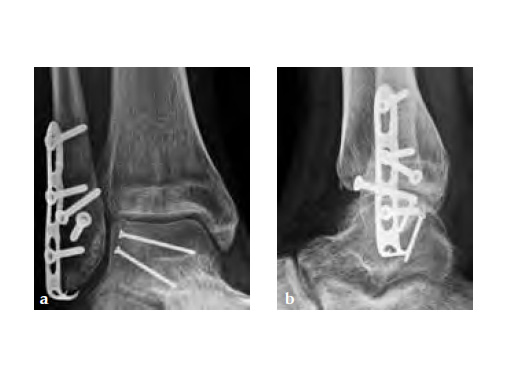

The LCP hook 3.5 enables tension-band plating with use of 3.5 mm screws. The hooks aid fixation of small bone fragments and increase stability. Elongated LCP holes make the plate and its fixation more flexible and allow for controlled compression. The spring effect facilitates reduction and a stable tension-band technique. Its flexible one-third tubular plate design provides an anatomical fit and its low profile minimizes hardware prominence.

The LCP hook 3.5 was primarily intended for treatment of simple fractures of the olecranon and osteotomies of the olecranon for distal humerus fracture treatment creating compression with the long oblique 3.5 mm lag screw. But it has shown its benefits also in avulsion fractures of the distal tibia and fibula.

A 20-year-old construction worker fell from a 3 m height. He sustained a typical posterolateral impression and flake fracture of the talar dome.